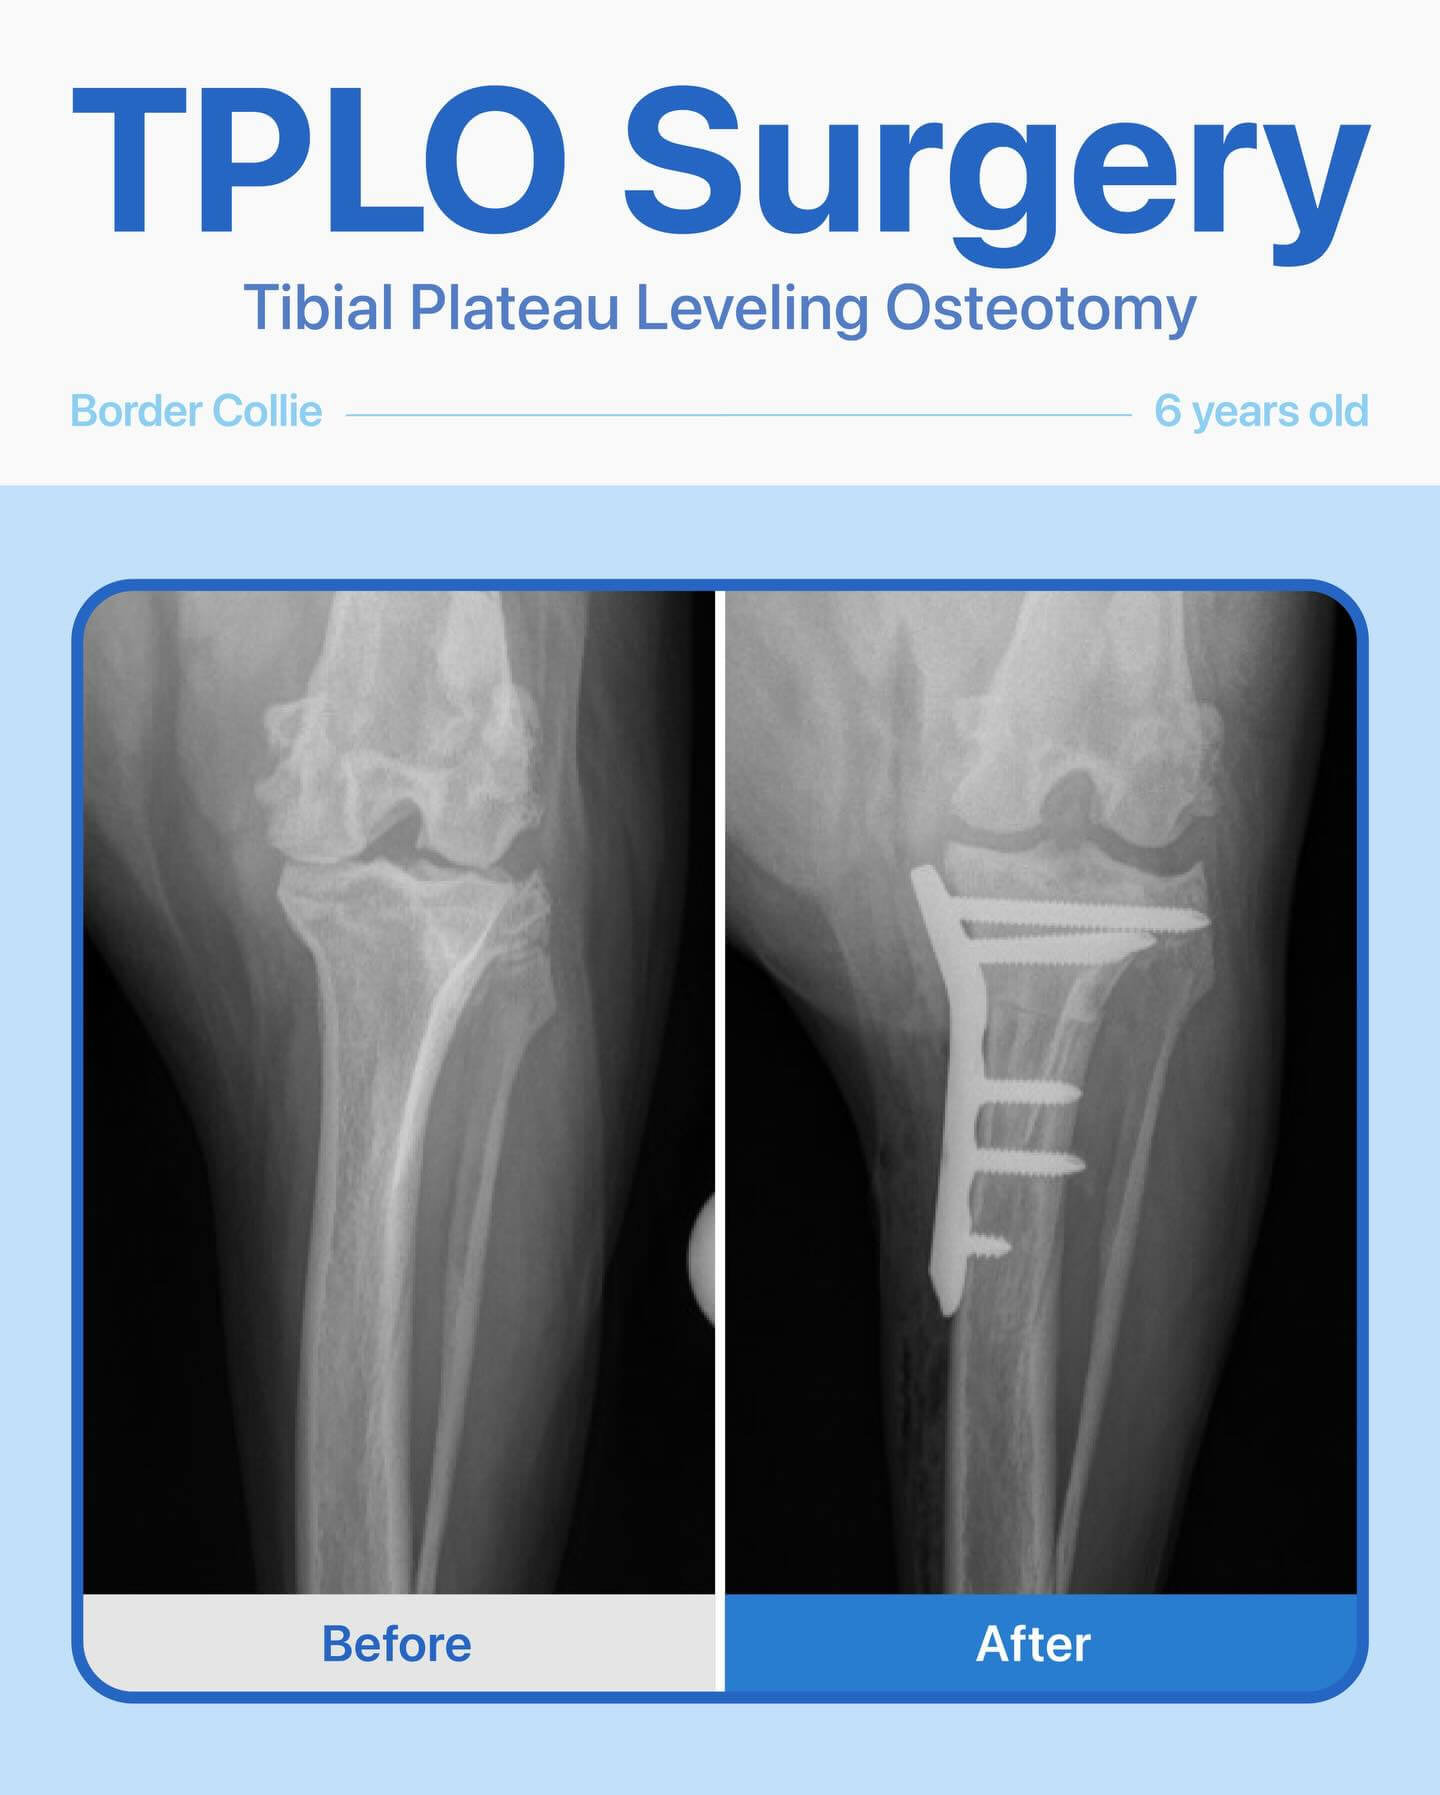

After radiographs and a thorough orthopedic exam, our team diagnosed a torn cranial cruciate ligament (CCL). To restore stability to her knee and help her return to an active, pain-free life, TPLO surgery was recommended.

The surgery was a success, and her recovery has been wonderful. She has healed beautifully and is now walking comfortably again—no pain, just happy steps forward.